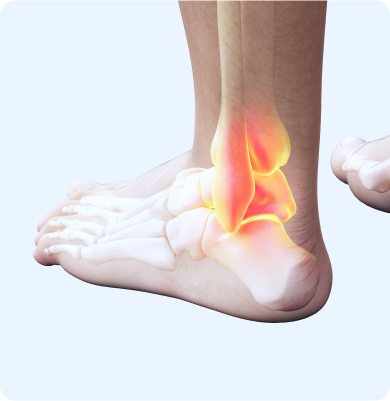

발목을 지지하는 인대가 외부 충격이나 과도한 움직임으로 손상되는 질환

운동 중 발을 접질리는 경우, 울퉁불퉁한 지면에서 걷거나 뛸 때, 하이힐 착용 등으로 인해 발목이 갑자기 비틀리며 인대에 과도한 긴장이 가해지면서 손상됩니다.

발목을 구성하는 뼈와 뼈 사이에 있는 연골이 손상되는 질환

발목에 직접적인 충격이나 비틀림 동작, 과도한 운동량 등이 원인입니다. 특히 스포츠 활동이나 사고로 인한 발목 염좌, 골절 등이 발목 연골 손상을 유발할 수 있습니다.

발목을 구성하는 뼈와 뼈 사이의 연골이 손상되어 염증이 생기고 시간이 지나면서 점차적으로 발목 관절의 기능이 떨어지는 질환

발목에 반복적인 부하가 가해지거나 이전에 발생한 발목 부상, 특히 골절이나 염좌로 인해 관절의 구조가 변형될 때 발생합니다.

관절내시경 수술(인대봉합술, 인대재건술), 인공관절 수술, 발목유합술, 무지외반증 교절술, 연부조직재건술, 근막유리술, 골극제거술, 활막제거술

체외충격파 치료, 도수치료